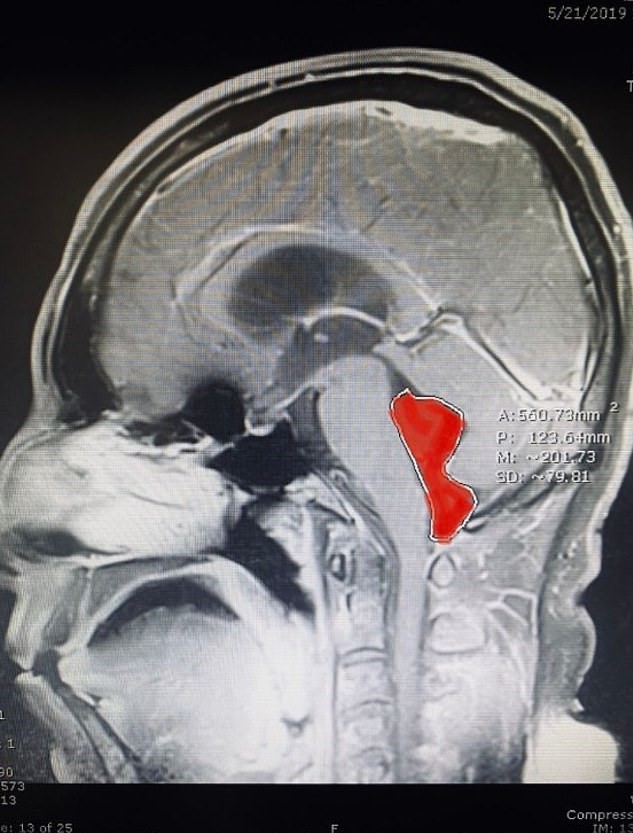

Thanks to a brain scan, neurosurgeon Dr. Jordan Amadio and the team were able to discover a 1.6” tapeworm lodged in the area near the patient’s brain stem.